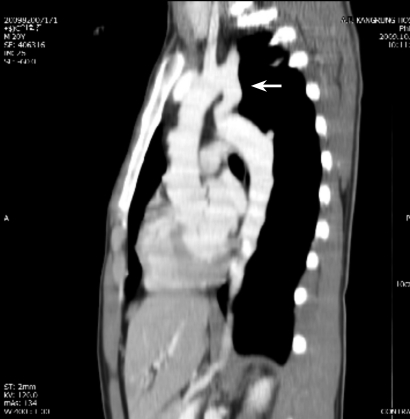

A chest CT was performed to evaluate supra-diaphragmatic vessel abnormalities. The CT revealed a stenotic lesion in the isthmus of the aorta (Fig. 3). After making a diagnosis, multiple rib notchings were found on a chest X-ray (Fig. 4). The patient was transferred to another university hospital for surgical treatment.

Figure 3

Sagittal contrast enhanced chest computed tomography shows stenosis in the isthmus of aorta (arrow).